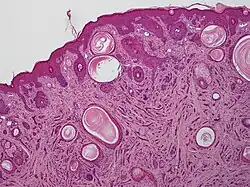

A microscopic view of microcystic adnexal carcinoma